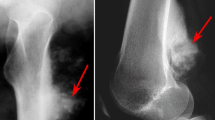

All patients were followed up from 25 to 42 months (mean, 33 months) and all 8 patients were alive at the time of reporting. The Musculoskeletal Tumor Society (MSTS) score was between 21 and 30 at the last follow-up16 and the mean knee flexion was 112.5° (range, 90°–130°, Table 2). It should be noted that the MSTS score is a common method for evaluating the postoperative evaluation of osteosarcoma surgery16. At the 2-year follow-up check, the patient was alive and living well without the evidence of recurrence. A plain X-ray film revealed that the bone defect was healed and no bone tumor was identified (Figs 1H and 10). The X-ray scan showed that using the individual templates resulted in the surgery with a high degree of precision, but without the cases of intramedullary nail misplacement (Fig. 10). The implants were stabilized and could bear sufficient weight to allow patients to eventually recover normal physical activity.

A 21-year-old patient with osteosarcoma of the distal femur.

(A) Anteroposterior CT scan image. (B) MRI image. Both CT and MRI images revealed an osteosarcoma in the left distal femur. (C) Merging of the CT and MRI images for the delineation of the tumor. (D) The 3-D bone tumor model reconstructed from the merged CT and MRI image with the tumor profile highlighted in red.